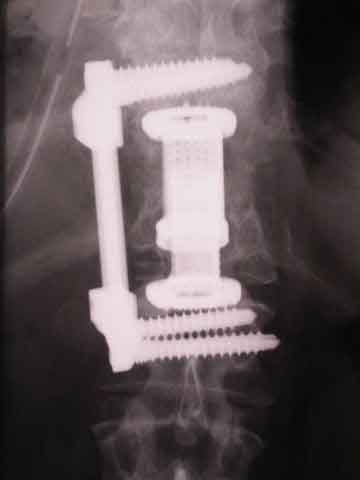

Hier wurde ein ganzer Wirbel entfernt und durch ein Implantat ersetzt. Ein solcher Eingriff ist bei Tumorbefall, komplizierten Wirbelbrüchen und Knocheneiterungen notwendig; zum Beispiel bei Tuberkulose.